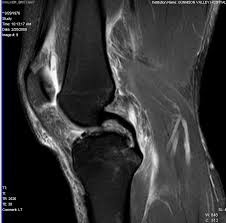

Μερικές εικόνες από μαγνητικές με ρήξη του προσθίου χιαστού συνδέσμου

Και με ακέραιους τους δύο χιαστούς